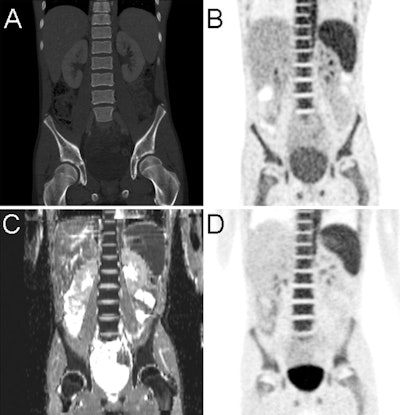

PET/MRI and PET/CT achieved similar lesion detection rates, the researchers found. There were 62 areas of focal FDG uptake on PET/CT images in 12 of the 20 scans. PET/MRI detected 61 (98%) of those areas, the lone exception being one lung lesion with focal uptake that was discovered only on PET/CT.

As expected, MRI's higher soft-tissue contrast was able to identify diagnostic information in lesions that were interpreted as negative with PET.

Conversely, CT discovered multiple lung metastases in two patients with sarcoma, which were only partly visible with MRI. PET/MRI also upstaged two pediatric cancer patients and found recurrence in two other children, resulting in a possible change in patient management.